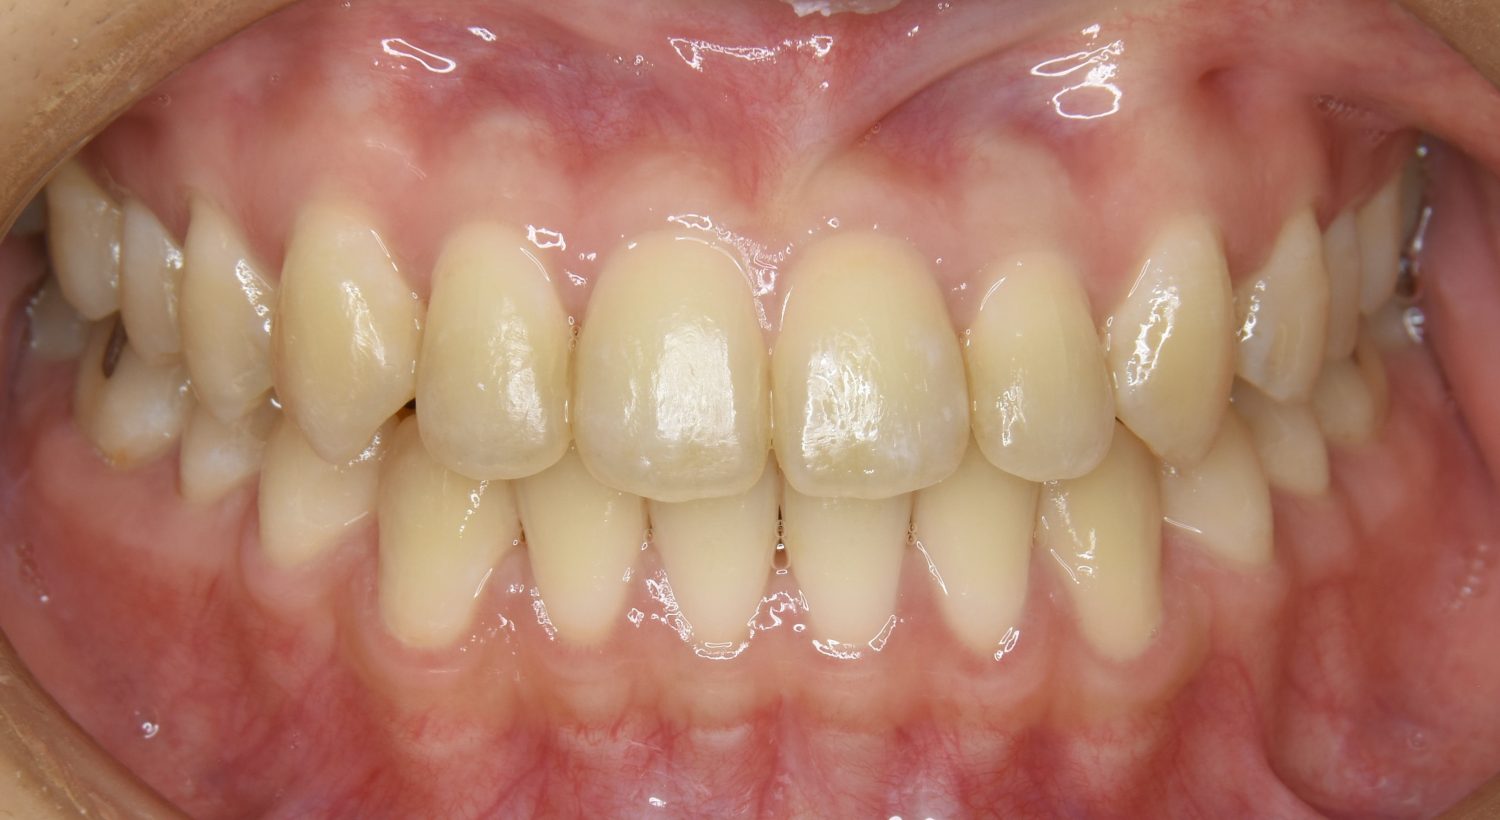

前歯部開咬の症例紹介①

After

主訴

前歯が開いているのが気になる。

治療内容

上リンガルブラケット(舌側装置)、下ラビアルブラケット(唇側装置)に矯正用アンカースクリューを併用し非抜歯で治療を行いました。

上下の前歯が開いており前歯では全く噛めていない状態でした。臼歯の圧下を行うことで前歯でも咬合できるようになり機能面のみでなく審美面も著しく改善しました。